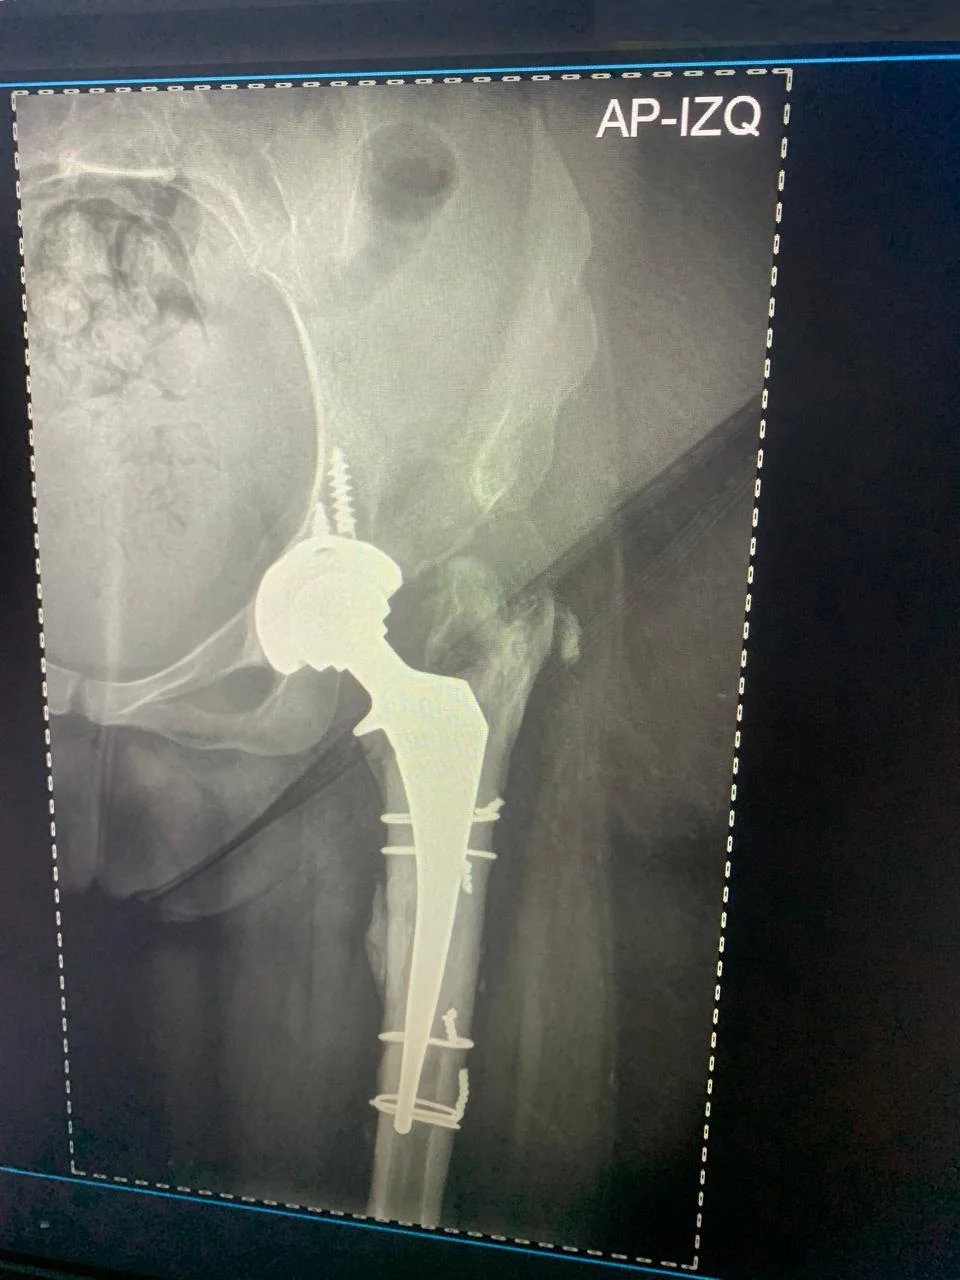

Antes Radiografía preoperatoria mostrando desgaste articular severo en cadera derecha - Dra. Ana Luz Bernabe

Después Radiografía postoperatoria de reemplazo total de cadera derecha exitoso - Dra. Ana Luz Bernabe

Reemplazo Articular

Artroplastia Total

de Cadera Derecha

• Perfil del Paciente: Femenino, 29 años. Cuadro de dolor severo de larga evolución.

• Diagnóstico: Limitación funcional severa para la marcha y actividades de la vida diaria.

• Procedimiento: Reemplazo total de cadera izquierda.

• Evolución (3 años): Reintegración total a sus actividades con excelente estabilidad y ausencia de dolor.